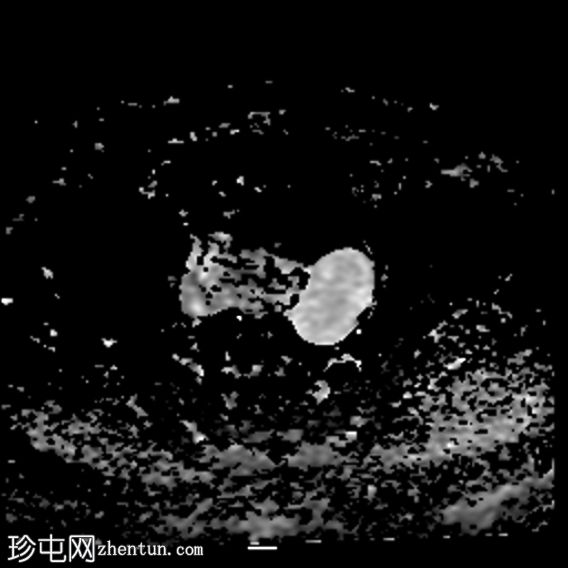

DWI

4.jpg

左侧卵巢增大,呈弥漫性低T1信号和高T2信号,可见周边卵泡,部分卵泡除周边卵泡周围有环状强化外,无明显实质强化。左侧附件蒂呈漩涡状,提示卵巢扭转。